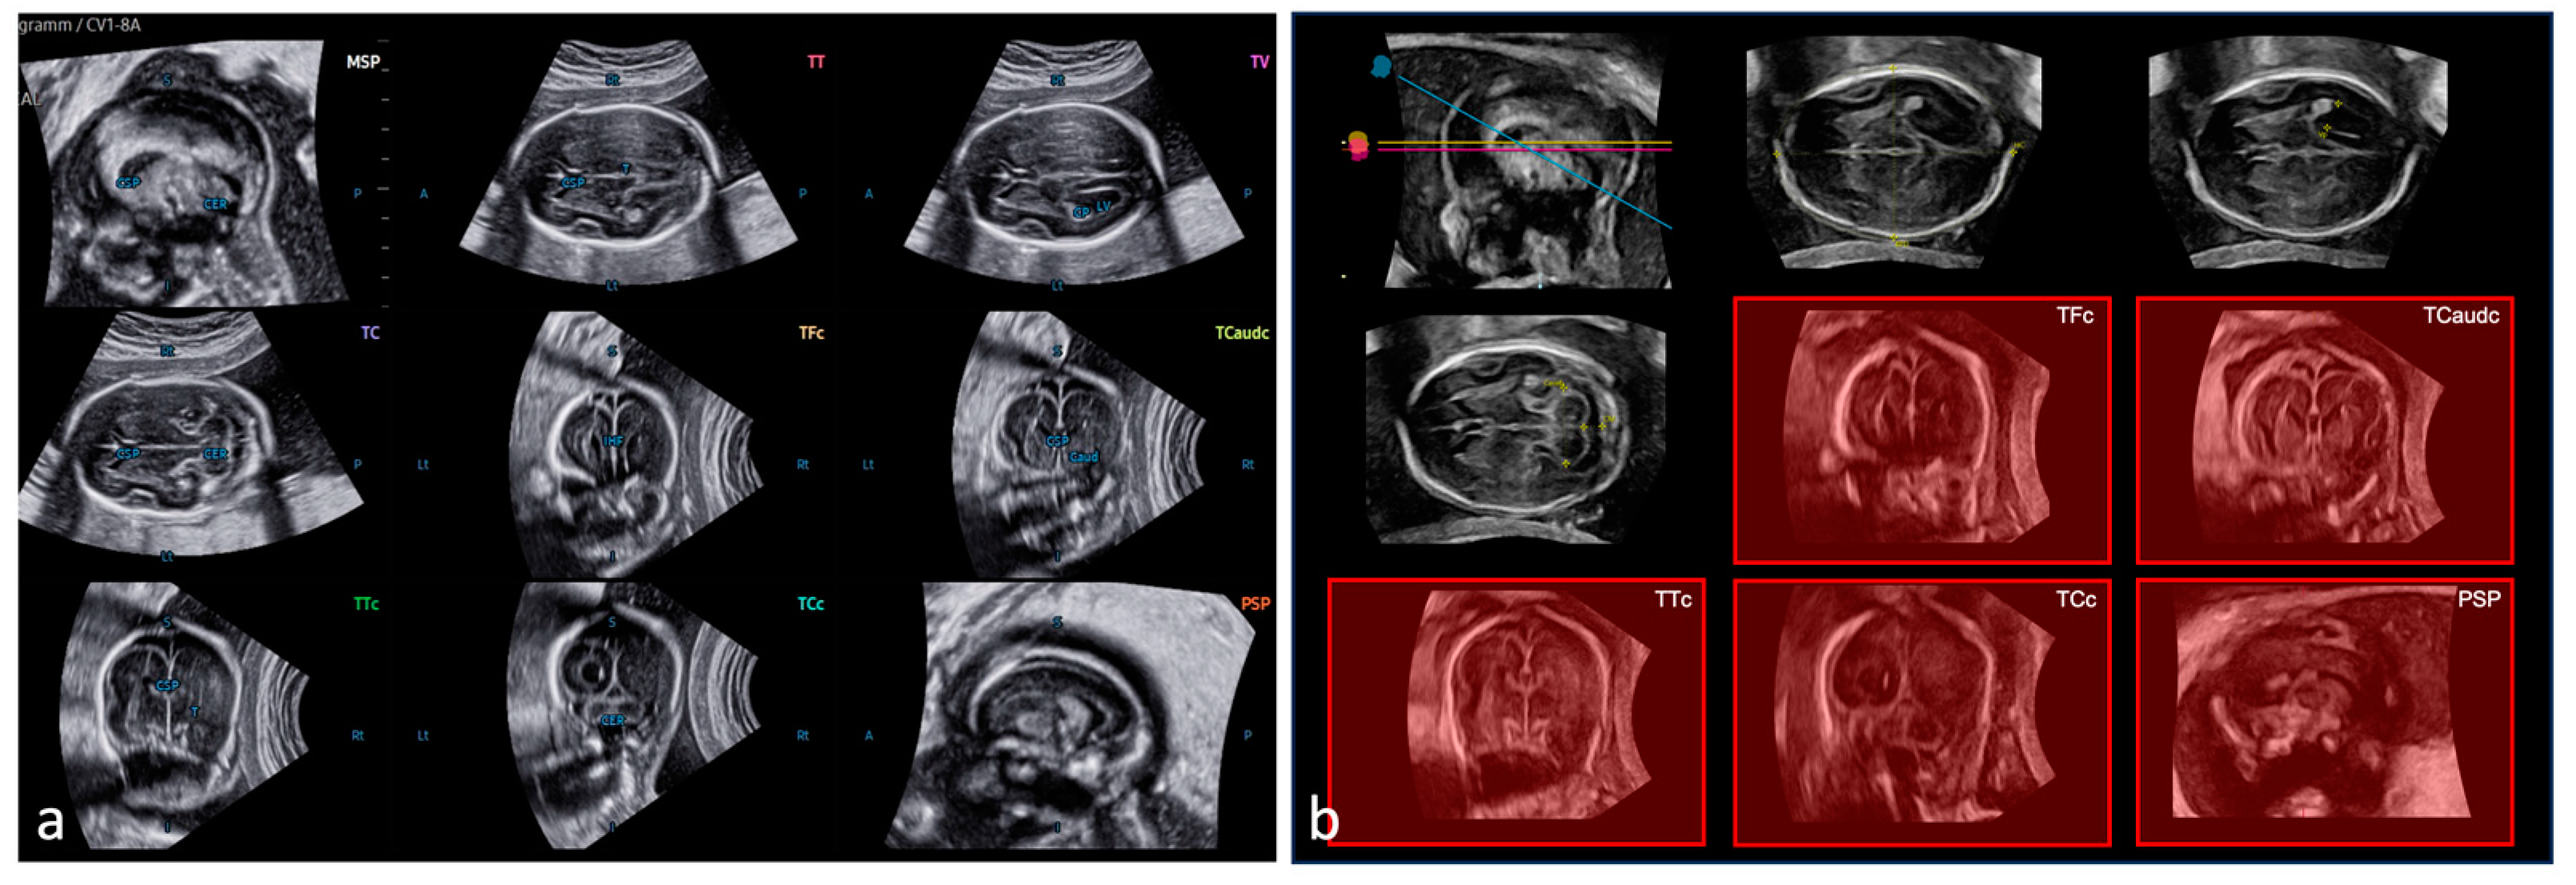

2.2. SonoCNS™

2.3. 5DCNS+™